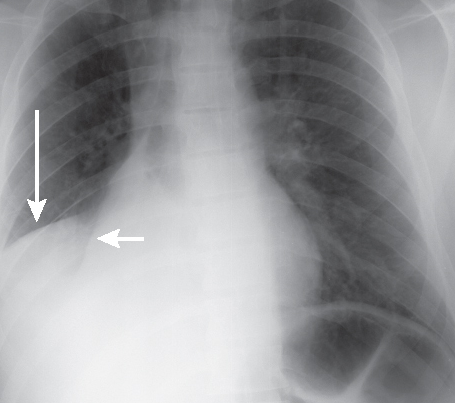

The initial evaluation or diagnosis of the syndrome may include a lateral view chest X-ray. However, sometimes there may also be an exhibition of plain films in patients with recurrent pneumonia, which is normal.

An evaluation based upon radiography may also imply. However, it will never lead to the underlying cause of the syndrome. Total blood count, bronchoscopy or/and CT(computed tomography) chest are some medical methods used to help further in elucidating the actual disease process behind. Another diagnosis of it is the right heart border obscured in both AP or PA projections.